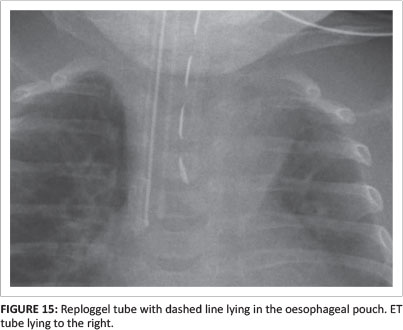

Reploggel suction catheters are used in patients with oesophageal atresia to remove saliva from the blind ending oesophageal pouch. The markings of a Reploggel tube form a dashed line, and help to differentiate it from the ETT (Figure 15).